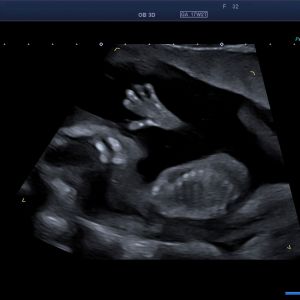

Früher Fehlbildungsultraschall / Ersttrimesterdiagnostik

Viele schwerwiegende komplexe Fehlbildungen können bereits früh erkannt werden. Ein unauffälliger Befund kann somit zu einer deutlichen Reduktion von Sorgen und Ängsten beitragen. Bei auffälligem Ultraschallbefund kann eine weiterführende Diagnostik zeitnah erfolgen.

Nackentransparenzmessung

Ziel dieser Diagnostik ist eine Wahrscheinlichkeitsberechnung für das individuelle Risiko ihres Kindes an einer Chromosomenstörung wie zum Beispiel der Trisomie 21 (Down- Syndrom) erkrankt zu sein. Dazu wird in der 11+0 bis 13+6 Schwangerschaftswoche die sogenannte Nackentransparenz (eine Flüssigkeitsansammlung unter der Haut im Nackenbereich des Kindes) gemessen. Unter Berücksichtigung des mütterlichen Alters, des Schwangerschaftsalters, der Dicke der Nackentransparenz und biochemischer Parameter (ß-HCG und PAPP-A) wird ein statistisches Risiko für das Vorliegen bestimmter Chromosomenstörungen errechnet. Sowohl falsch- positve als auch falsch- negative Vorhersagen sind möglich.